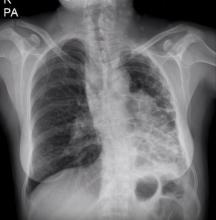

A 41-year-old female patient with a 20-year history of bronchiectasis presented at the authors’ clinic with recurrent hemoptysis and frequent pulmonary infections. A CT scan showed that the patient's left lung was destroyed. A pneumonectomy was the only option for surgical resection, and the authors decided to perform a VATS pneumonectomy to minimize morbidity. As a result of recurrent infections, there were severe, dense pleural adhesions. The patient was discharged on postoperative day five, and was followed up with no complications.